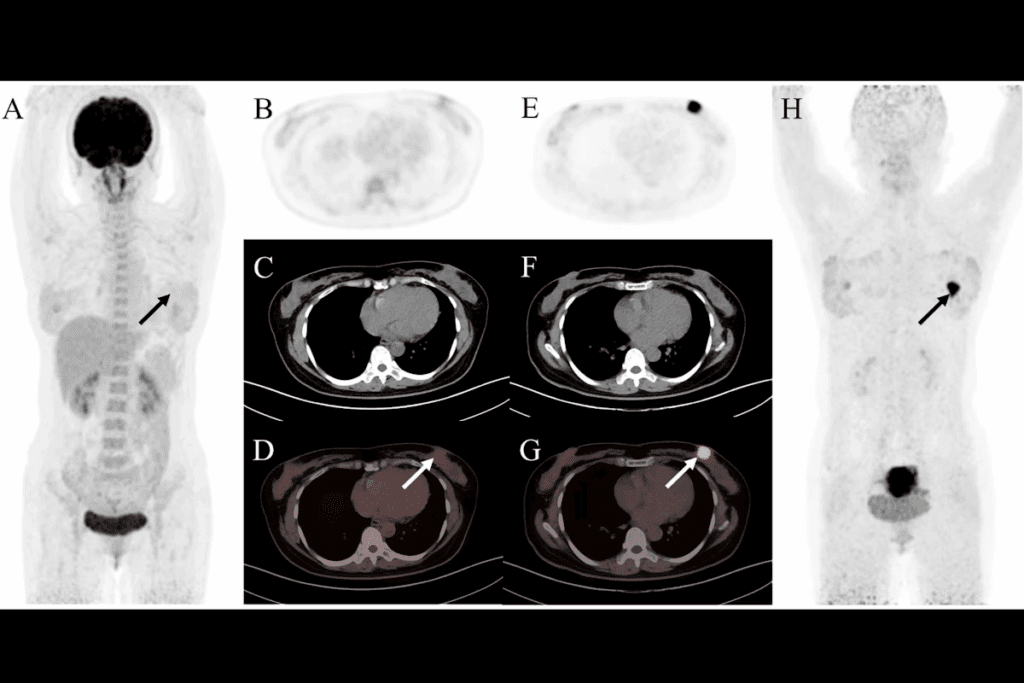

CT-guided biopsy is a new way to get tissue samples for medical tests. It uses CT scans to guide a needle into the right spot. This makes sure the samples are accurate.

A CT scan biopsy, or CT-guided needle biopsy, uses CT scans to guide the needle. It helps get tissue or fluid samples from hard-to-reach places in the body. This is great for diagnosing problems in organs or tissues.

The CT scanner shows real-time images. This helps doctors place the needle exactly where it needs to be.

CT-guided biopsy is used for many health issues. It’s good for checking on lung, liver, kidney, and lymph node problems. It helps find cancers, infections, and inflammatory diseases.

Real-Time CT Guidance Techniques

We use real-time CT guidance throughout the procedure. This means we get continuous CT scans. These scans show us where the needle is in relation to the tissue.

This feedback lets us make precise adjustments. It ensures we get the tissue sample from the right spot.